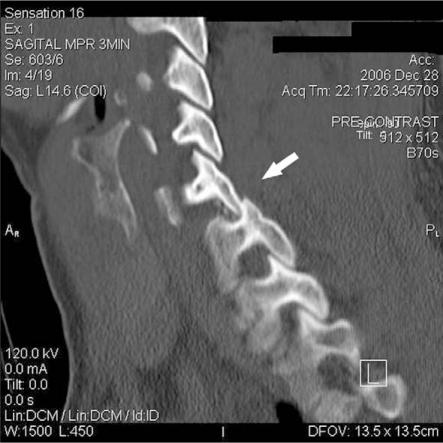

一种用于开放性复位颈椎创伤性单侧小关节交锁的撬拨技术:技术说明

A levering technique for open reduction of traumatic unilateral locked facets of cervical spine: technical note.

Reduction of traumatic unilateral locked facets of the cervical spine can be accomplished by closed or open means. If closed reduction is unsuccessful, then open reduction is indicated. The previously described techniques of open reduction of a unilateral locked facets of the cervical spine in the literature included drilling facet, forceful manipulation or using special equipment. We describe a reduction technique that uses a basic spinal curette, in a forceless manner, and it does not need facet drilling. We have successfully used this technique in 5 consecutive patients with unilateral locked facets. There have been no complications related to this technique.

颈椎创伤性单侧小关节交锁的复位可通过闭合或开放方法完成。如果闭合复位不成功,则需行开放复位。文献中先前描述的颈椎单侧小关节交锁的开放复位技术包括磨钻关节突、强力手法复位或使用特殊设备。我们描述了一种使用基本的脊柱刮匙、以无暴力方式且无需磨钻关节突的复位技术。我们已连续5例单侧小关节交锁患者成功应用该技术,且未出现与该技术相关的并发症。